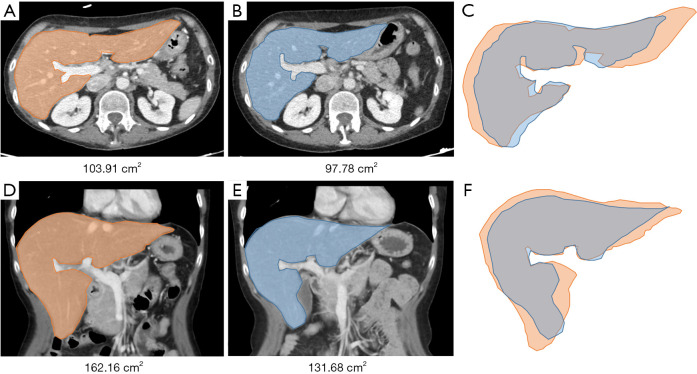

Methods: Databases at two institutions were queried, and 74 CLM patients who underwent preoperative chemotherapy and curative PSH were reviewed. Pre- and post-chemotherapy total liver volumes (TLVs) were computed with Synapse 3D software, and the degree of atrophy was calculated as the difference in percentage. The cut-off value for significant degree of atrophy was set at 10%. Risk factors for post-chemotherapy liver atrophy were assessed using logistic regression, while multivariate analysis was computed to identify risk factors for postoperative complications.

Abstract Image